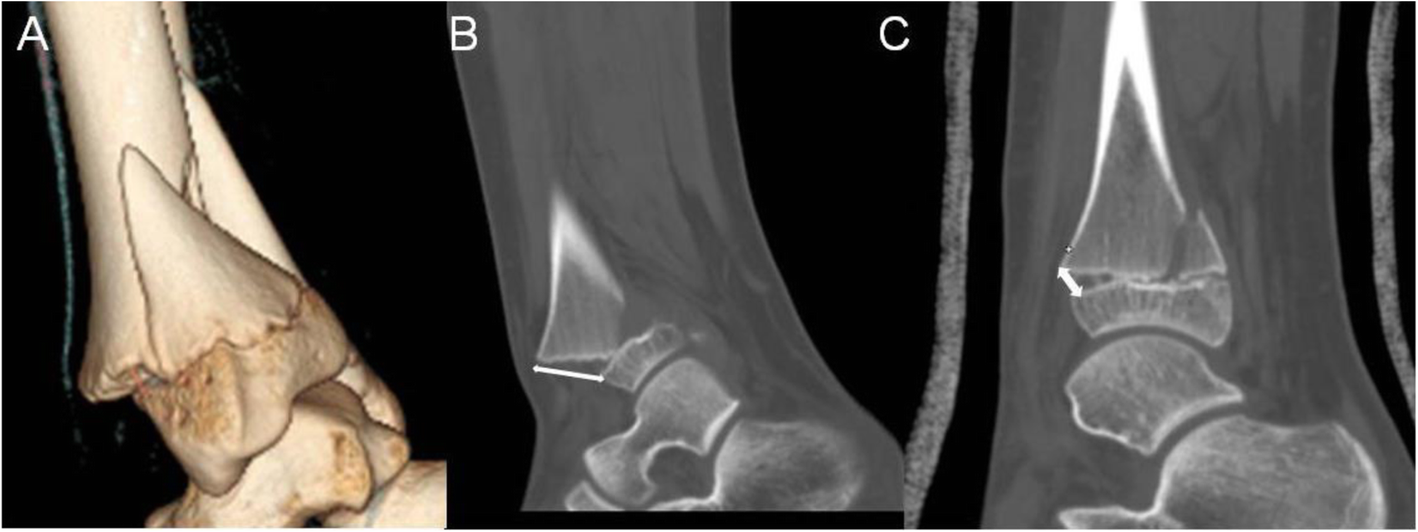

Fig. 1

A 13-year-old boy fell downstairs and suffered a twist to his right ankle. a 3D CT view showed a displaced S-H II distal tibia fracture. b The maximal distance of displacement of the fracture was 18 mm (white double arrow) demonstrated in sagittal view. c The residual displacement was approximate 5 mm after closed reduction and casting